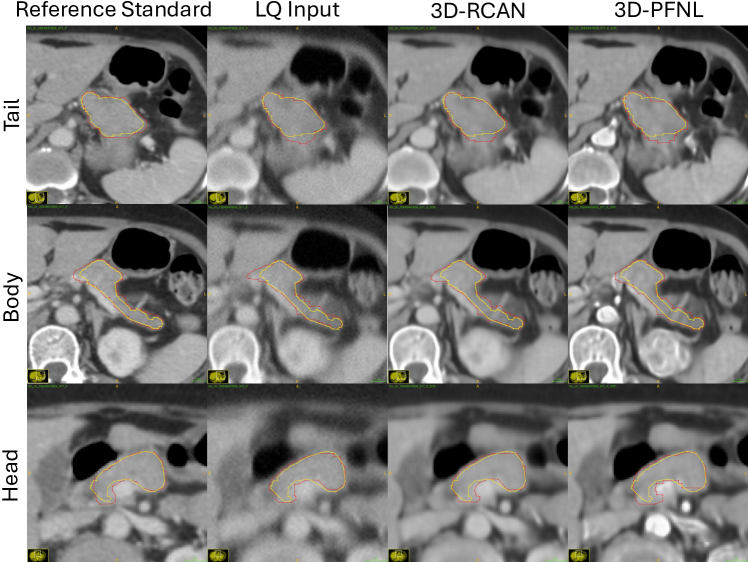

Refer to caption

Figure 4: Segmentation results of TotalSegmentator (TS) on the reference (original) portal venous (PV) CT scan, low-quality (LQ) PV CT, 3D-RCAN restored PV CT and 3D-PFNL restored PV CT, respectively. Manual pancreas annotations are in yellow, while the automated segmentations by TS are in red.

Fig. 3 shows the distribution of Dice scores and NSD for pancreas segmentation by TS on the reference (original) PV CT, low-quality (LQ) PV CT, 3D-RCAN restored PV CT, and 3D-RFNL restored PV CT, respectively. From Table II, the reference corresponded to the baseline performance of TS on the original PV CT for pancreas segmentation. However, when TS was executed on the degraded low-quality PV CT, the Dice score and NSD dropped to 68.9 ±plus-or-minus\pm± 19.3 and 22 ±plus-or-minus\pm± 8, respectively. After PV phase quality enhancement with 3D-RCAN, the Dice score and NSD improved by approximately 1.9% and 2%, respectively. Moreover, quality enhancement with 3D-PFNL further improved the Dice score by approximately 2.8% and NSD by 3%. Moreover, 3D-PFNL attained a lower standard deviation in Dice scores compared to both LQ and 3D-RCAN. The confidence interval of Dice score and NSD obtained by 3D-PFNL are [0.6299, 0.7725] and [0.2066, 0.2869] respectively.

Compared against LQ, results from 3D-PFNL on the restored PV CT were statistically significant for both Dice score (p = .034) and NSD (p = .025). The Dice score on the restored PV CT was also significant for 3D-RCAN (p = .007). Notably, TS failed to segment the pancreas in one LQ PV CT. After quality enhancement with 3D-PFNL, TS segmented the pancreas in the same volume. Fig. 4 shows an example. The pancreatic body (second row in Fig. 4) and tail (first row) tended to be over-segmented, while the pancreas head (third row) was under-segmented. After quality enhancement, TS segmented most of the pancreas with minor errors.